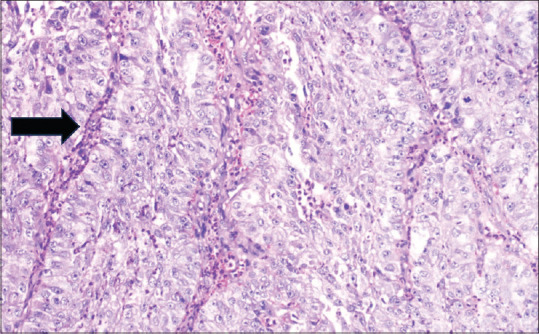

Carcinoma of the nose and paranasal sinuses is an uncommon tumour accounting for less than 1% of all malignancies and about 3% of head and neck malignancies. It is more common in fifth and sixth decades with increased male preponderance. Occupational exposure to nickel has been known to increased its occurrence. Here we present a case of 25-year male presenting with right sided nasal blockage and pain in the right eye with swelling for 2 months. Imaging studies revealed a large soft tissue density with involvement of surrounding structures with bony erosion and extension to the orbit. Histopathology and Immunohistochemistry confirmed the diagnosis of poorly differentiated sinonasal carcinoma non keratinising type.